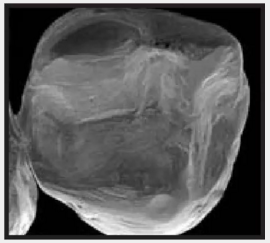

復(fù)合樹脂在即刻充填后,觀察其在電子顯微鏡下的掃描圖像,本次研究選擇了9種具有代表性的復(fù)合樹脂材料。

Heliomolar(研究控制組) Ivoclar Vivadent 義獲嘉維瓦登特

7.png